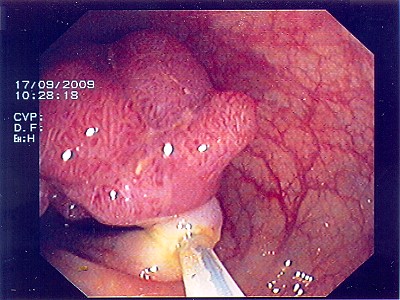

Wie bei den Abbildungen 28 und 30 handelt es sich um einen breitbasigen, relativ flachen, noch nicht entarteten Polyp, der sich mit einer Schlinge nicht vollständig abtragen ließe.

Wie bei den Abbildungen 29 und 31 erfolgt hier nach einem speziellen kombinierten Manöver (laparasko typisch gestützte Koloskopie - gleichzeitige Bauch- und Darmspiegelung), Entfernung des Polypen weit im Gesunden mit einem speziellen Klammernahtgerät. Die hier gut abgebildete Klammernahtreihe bleibt zurück. Der Eingriff erfolgt - wie gesagt - in so genannter Schlüssellochtechnik, aber auch mit unterstützender Darmspiegelung.